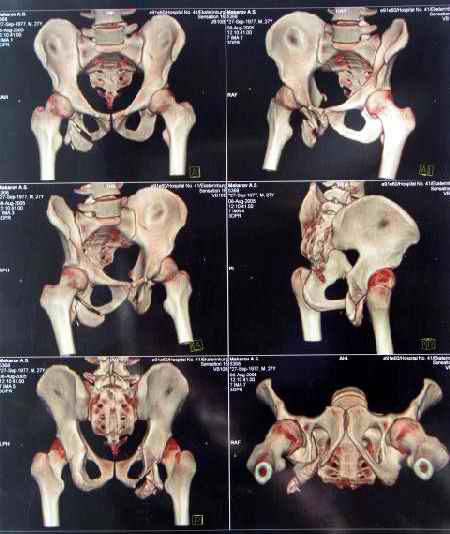

Уважаемые коллеги, хотелось бы услышать ваше мнение по тактике лечения следующего пациента: мужчина, 27 лет, получил травму на производстве 25 июня - перелом правого седалищного бугра (кт и рентгенограмма прилагаются).

Больной жалуется на боли - сидя и при ходьбе. В настоящее время ходит, хромая, без дополнительной опоры. Оторвавшийся седалищный бугор состоит из 2-х фрагментов, один из которых раздражает седалищный нерв. Если кто-то имеет опыт оперативного лечения подобных повреждений, подскажите из какого доступа лучше это сделать. Заранее спасибо.